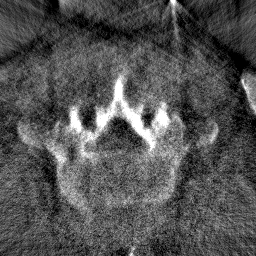

2D segmentation. Our model is compared with two methods based on domain adaptation: AdaptSegNet [16] and SIFA [2]. AdaptSegNet and SIFA are trained with the officially released codes. AdaptSegNet is trained with Dice loss as we only have one class here. The results are summarized in Fig. 6 and Table 2(a). AdaptSegNet invokes DeeplabV2 as the segmentor and cannot capture the vertebra especially when metal artifacts exist. SIFA outputs plausible predictions but the performance is heavily affected by the metal artifacts. Also, the segmentations predicted by SIFA can not capture vertebrae precisely and show false positive bones and enlarged masks (see red arrows in Fig. 6). With joint learning, our model achieves the best segmentation performance with an average Dice of 0.847 and an average ASD of 1.54mm.

Modality translation and artifact reduction. Here we compare our model with other methods: CycleGAN [21], DRIT [8], ADN [9]. All the models are trained with our data using their officially released codes. Further, we train a UNet segmentation network using annotated CT data and apply it to synthesized CT images as an anatomy-invariant segmentation evaluator. As shown in Table 2(b), our model achieves the best performance with a much larger average Dice compared with other methods. Fig. 6 shows the synthetic images and segmentation results. CycleGAN and DRIT tend to output plausible and realistic CT images but are not able to preserve the anatomical information precisely. As shown by the red arrows in Fig. 6, the bony structures appear distorted and noisy. ADN can retain most of the anatomical information but not for the bone pixels with high intensity, which might be classified into metal artifacts. With anatomical knowledge learned from the CT domain, our model outputs high-quality synthetic CT images while keeping anatomical consistency.

For artifact reduction, ADN and DRIT [8] could not successfully recover the clean images and streak artifacts remain in the synthetic image (see blue arrows in Fig. 6). CycleGAN [21] could output clean images but the distorted bones make them less valuable. Our model can suppress all the artifacts and keep the bone edges sharp, which outperforms all the other methods.